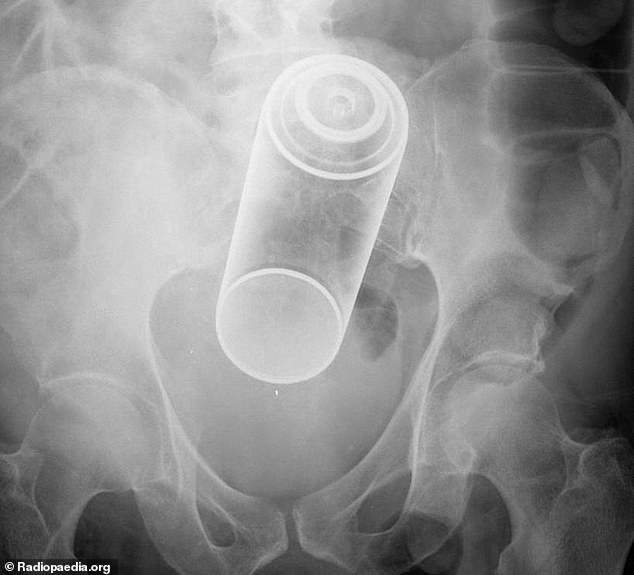

X光機下拍到的各種異物

肛門

・鐵樂士那種噴罐

・折疊刀

・長超過15CM的玩具

・牙刷、牙籤

・吸污清潔棒

・兩支刀片

・按摩棒或震動棒~兩支

・避孕套包裝紙

・把粉塵吹開的噴嘴

・打火機

・水槍

・煮蛋計時器

・洗髮精罐子(各種尺寸)

・電燈泡

・聖誕節裝飾物